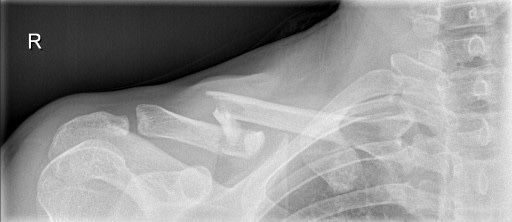

Also ich bin am Wochende mit der Evoc Weste über den Lenker und habe mir sofort das Schlüsselbein gebrochen, da die Evoc hier null schutz hat.

Davor kann dich eigentlich keine Weste schützen, die einigermaßen tragbar ist. Die Energie vom Aufprall muss ja irgendwo hin. Das Polster kann die nicht komplett aufnehmen. Was die Weste verhindert, sind z.B. Sehnenrisse und Brüche an der Schulter.